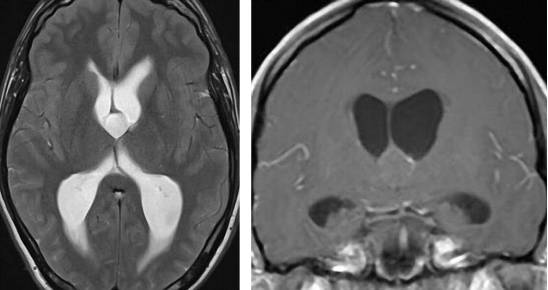

图4. 松果体细胞瘤在T2相上表现为高信号,伴有周围强化。松果体细胞瘤一般生长缓慢,偶尔需要手术干预。